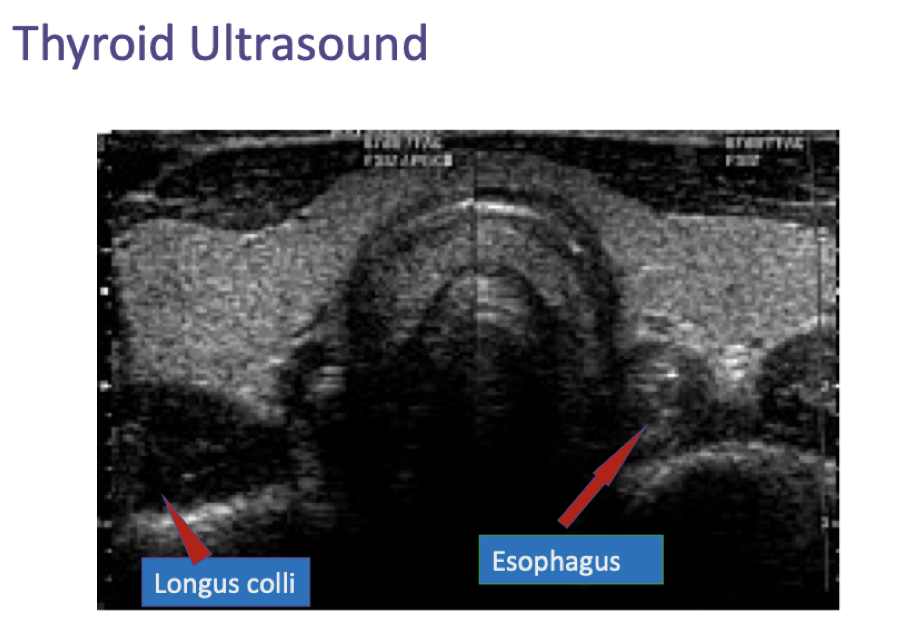

____ is the modality of choice for evaluation of thyroid structure, while ____ and ____ can provide functional information

Ultrasound is the modality of choice for evaluation of thyroid structure, while iodine / technetium isotope and PET can provide functional information

Ultrasound is used to characterize ____ in the thyroid

Ultrasound is used to characterize structural alterations in the thyroid